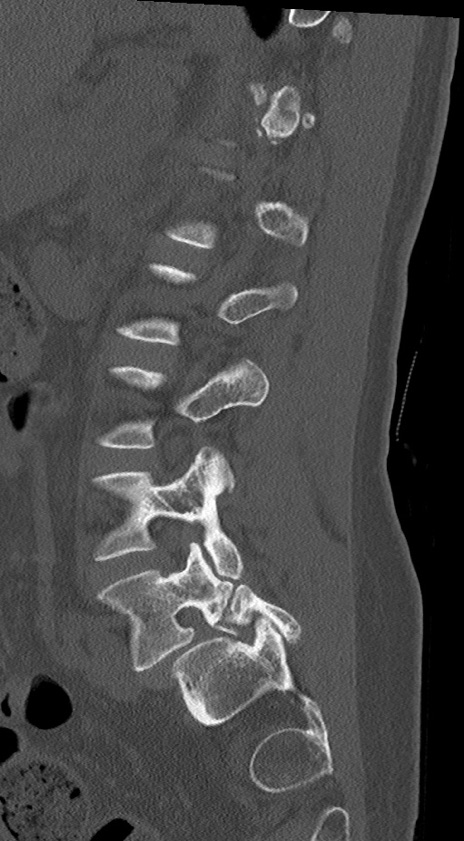

【整形】TIPS症例4 腰椎CT(矢状断像)

腰椎CT

冠状断像